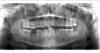

Ёжа Опубликовано 31 марта, 2011 Автор Поделиться Опубликовано 31 марта, 2011 (изменено) Вот обещанные подробные снимки. Сегодня были ещё в 2х независимых клиниках, говорят, что очень мало шансов зубу оставили, две очевидные ошибки, все сходятся во мнении, что остался инструмент поэтому канал до конца не прошел и разбит дистальный корень, плюс возможны внутренние трещины, и всё лечение без гарантий. http://radikal.ua/data/upload/0fccf/0fccf/039b4e707e_preview.jpg Изменено 31 марта, 2011 пользователем Ёжа Ссылка на комментарий

Petrovith Опубликовано 31 марта, 2011 Поделиться Опубликовано 31 марта, 2011 шансов вылечить без осложнений этот зуб очень мала,сломаный инструмент видно и достать его очень проблематично. Ссылка на комментарий

Ferny Опубликовано 31 марта, 2011 Поделиться Опубликовано 31 марта, 2011 (изменено) Видно, что инструмент сломан за областью фуркации корня, поэтому достать сломанный кусок инструмента будет проблематично, т.к если это делать даже под микроскопом то врач может и не увидить инструмента ?именно изза того что он находится за фуркацией) можно конечно попробовать ультразвуком...но не известно. В таком случае если пробовать расширять канал для того чтоб извлеч инструмент можно так же вызвать перфорацию. Если канад будет проходим в области сломанной иголки и при этом канал был хорошо продизенфицирован и использовался коффер, то можно заполнять его ( щас фидно на снимке что нижняя треть корня вобще не заполнена и видимо инфекция там есть. Дистальный корень скорей всего в будущем можно будет сделать хемисекцию, или пробовать обтурировать перфу МТА. Сломанная иголка это одна из комлекаций лечения, и часто от врача не зависит, бывает , как говорится, главное надо сообщить об этом пациенту и сказать возможные решения проблемы. Изменено 31 марта, 2011 пользователем Ferny Ссылка на комментарий

IRGL Опубликовано 31 марта, 2011 Поделиться Опубликовано 31 марта, 2011 достать обломок инструмента вообще не проблема, а перелом дистального корня - проблема зуб в плевательницу. хирургу удалявшему восьмой - физкультпривет.http://funportal.info/smiles/smile55.gif Ссылка на комментарий

juli63 Опубликовано 1 апреля, 2011 Поделиться Опубликовано 1 апреля, 2011 Вот обещанные подробные снимки. мда, беру свои слова обратно... жалко,но зуб в топку. Ссылка на комментарий